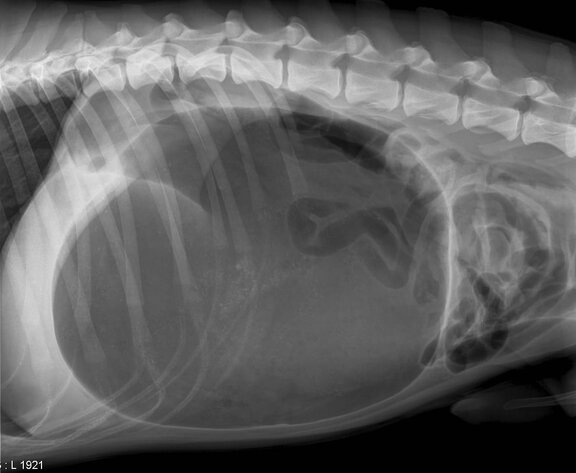

Um diese Wissenslücken zu schließen, muss man sich mit dem Wesen dieser Erkrankung vertraut machen: Vereinfacht ausgedrückt hängt der Hundemagen an Bändern befestigt in den Bauchraum hinein. Je größer der Hund ist, desto länger sind diese Bänder und desto größer ist die Gefahr. Nach der Fütterung ist der Magen schwer und voll und schwingt bei Bewegung wie ein Pendel im Bauchraum hin und her. Tobt der Hund nun mit gefülltem Magen wild auf der Wiese herum oder wird er im Spiel zu Hause über den Rücken auf dem Teppich herumgerollt, kann es passieren, dass sich der an den Bändern hängende volle Magen einmal um die eigene Achse verdrillt. So schnell kann es gehen, und schon ist die Magendrehung passiert. Oft wird in diesem Zusammenhang die Milz mitverdreht, da sie am selben Aufhängeapparat befestigt ist. Dies kann das Geschehen zusätzlich dramatisieren. Der Vorgang der Verdrehung an sich ist nicht schmerzhaft und zunächst auch nicht schlimm. Doch von allein dreht sich der Magen nun nicht mehr selbst zurück. Der darin enthaltene Futterbrei kann nicht mehr in den Darm weiterwandern. Es bildet sich Gas, was die Verdrehung zusätzlich verfestigt. Doch das ist noch nicht das Hauptproblem. Die eigentliche Krux an der Sache ist, dass die Blutgefäße, die die Magenwand versorgen, durch die Verdrillung abgequetscht werden. Die Magenwand wird nicht mehr mit Blut versorgt. In der Folge stirbt sie ab. Und ohne Magen kann ein Tier nicht leben.

Zunächst ist meist eine Fütterung vorangegangen, gefolgt von Bewegung, eventuell im Spiel mit Rollen über den Rücken. Die Symptome entwickeln sich in der Folge dieser Vorgeschichte dann rasch innerhalb von wenigen Stunden. Der Hund beginnt zu hecheln und wird unruhig. Der Bauch bläht zunehmend auf. Es kommt ein Würgereiz hinzu, ohne dass der Hund tatsächlich Mageninhalt erbricht. Beim vorsichtigen Abklopfen des Bauchraumes hört der Untersucher ein trommelähnliches, hohles Geräusch. Die Krankheitsanzeichen nehmen stetig zu, und das Allgemeinbefinden des Tieres wird schlechter. Jetzt ist schnelles Handeln gefragt. Denn ohne Operation geht es nicht. Es muss sofort ein Tierarzt oder, fast besser noch, eine Tierklinik aufgesucht werden, da nicht jede Tierarztpraxis zu jeder Tages- und Nachtzeit über Ausrüstung und Arbeitskräfte verfügt, eine derartige Operation durchzuführen. Der Bauch muss eröffnet, der Magen zurückgedreht und, um ein Rezidiv zu vermeiden, eventuell an der Bauchwand befestigt werden. Unter Umständen wird zudem die Entfernung bereits abgestorbener Organteile notwendig.